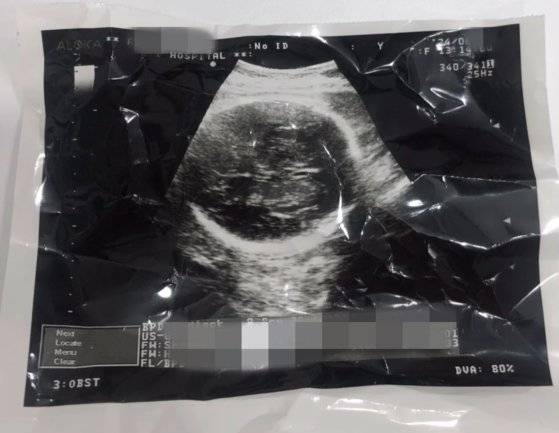

그는 초음파 검사를 받는 모습도 공개했다. 영상에는 의사가 초음파 진료를 보며 "심장 뛰는 것 봐라. 심장도 이렇게 잘 뛰잖아. 모르고 약을 먹거나 하진 않았죠? 이 정도면 낳아야 한다. 못 지운다"고 말하는 음성도 담겼다.